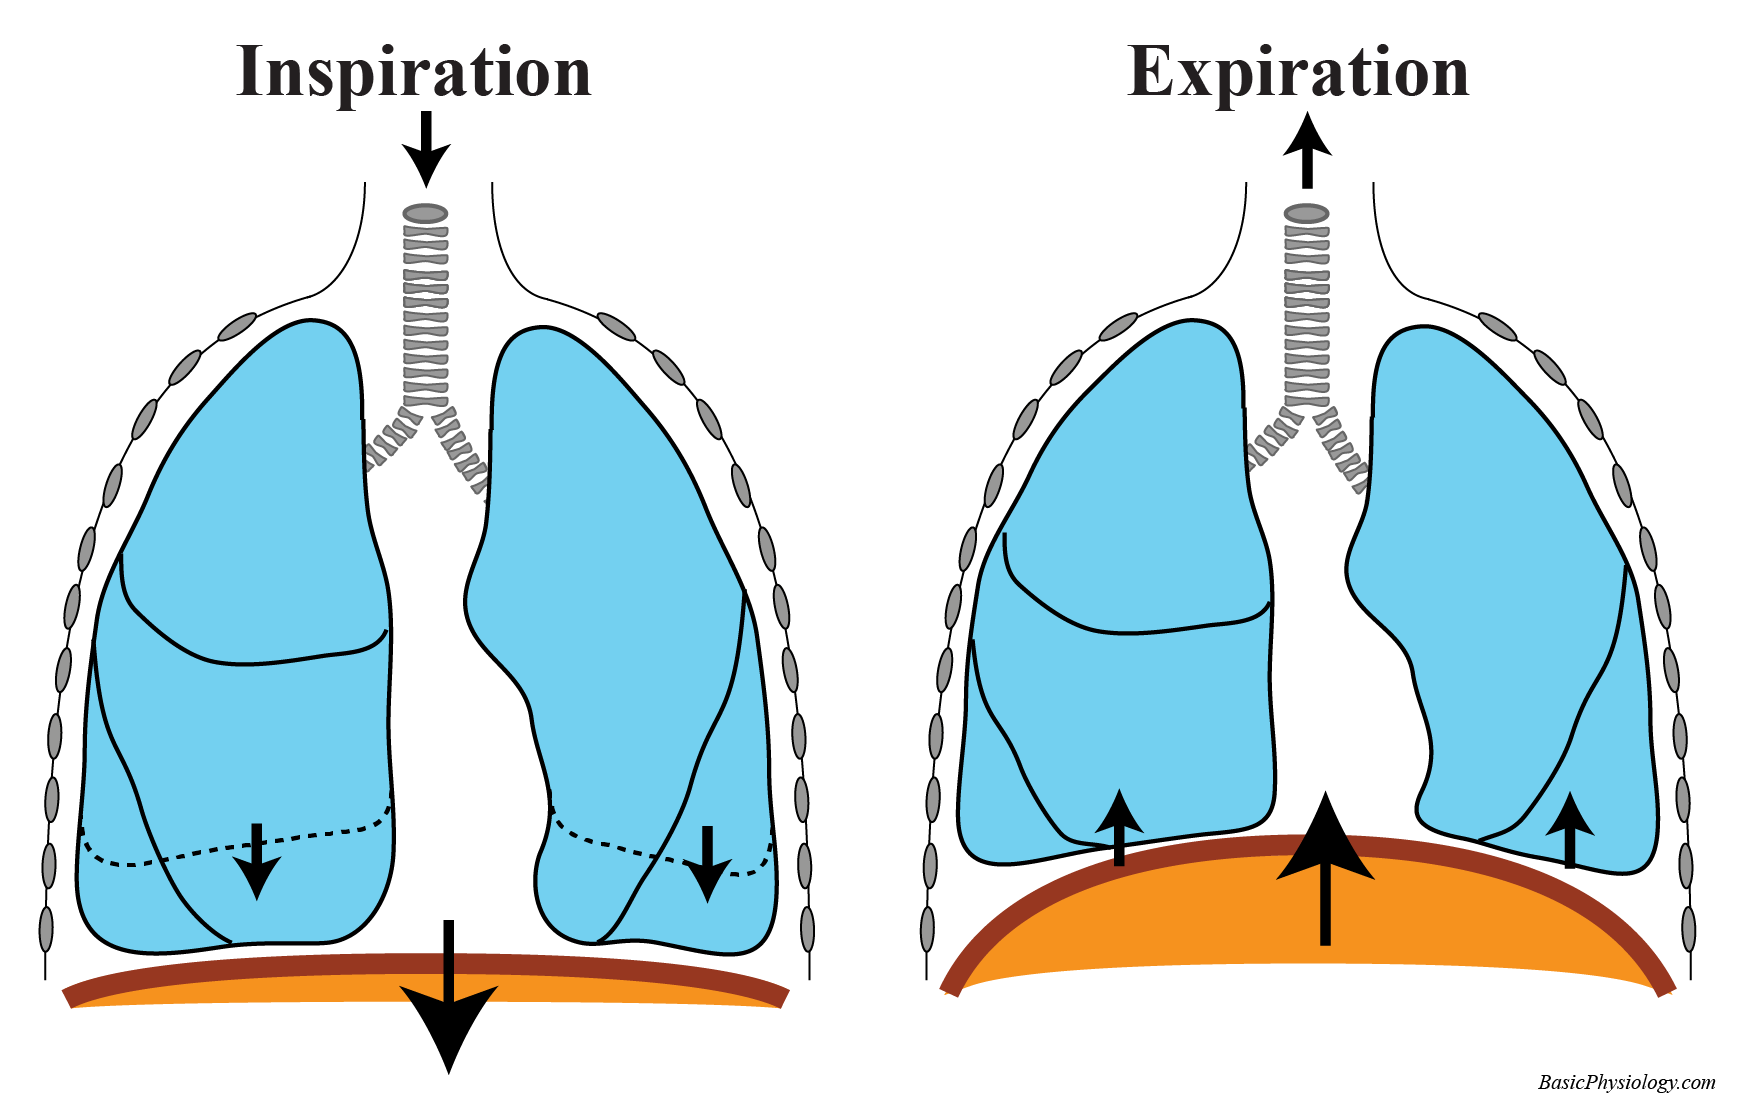

Normal Difference Between Chest Inspiration And Expiration

Normal Difference Between Chest Inspiration And Expiration

More picture related to Normal Difference Between Chest Inspiration And Expiration

Diaphragmatic Breathing Exercises Physiopedia

Diaphragm Definition

Diaphragm Breathing

Diaphragmatic Breathing Exercises Physiopedia

Normal Difference Between Chest Inspiration And Expiration - 2025 DIY